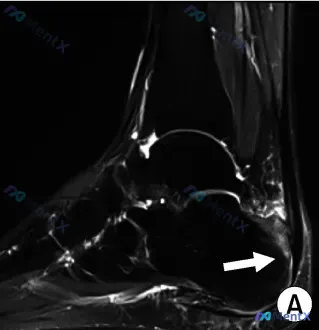

- 关键影像(Twin A 左踝矢状位 T2WI):

- 跟腱止点处信号异常增高(肌腱变性/炎症)

- 跟骨后上缘片状骨髓水肿(应力/炎症反应)

- 跟腱与跟骨之间局部高信号积液(跟腱后滑囊炎)

- 踝关节腔少量积液